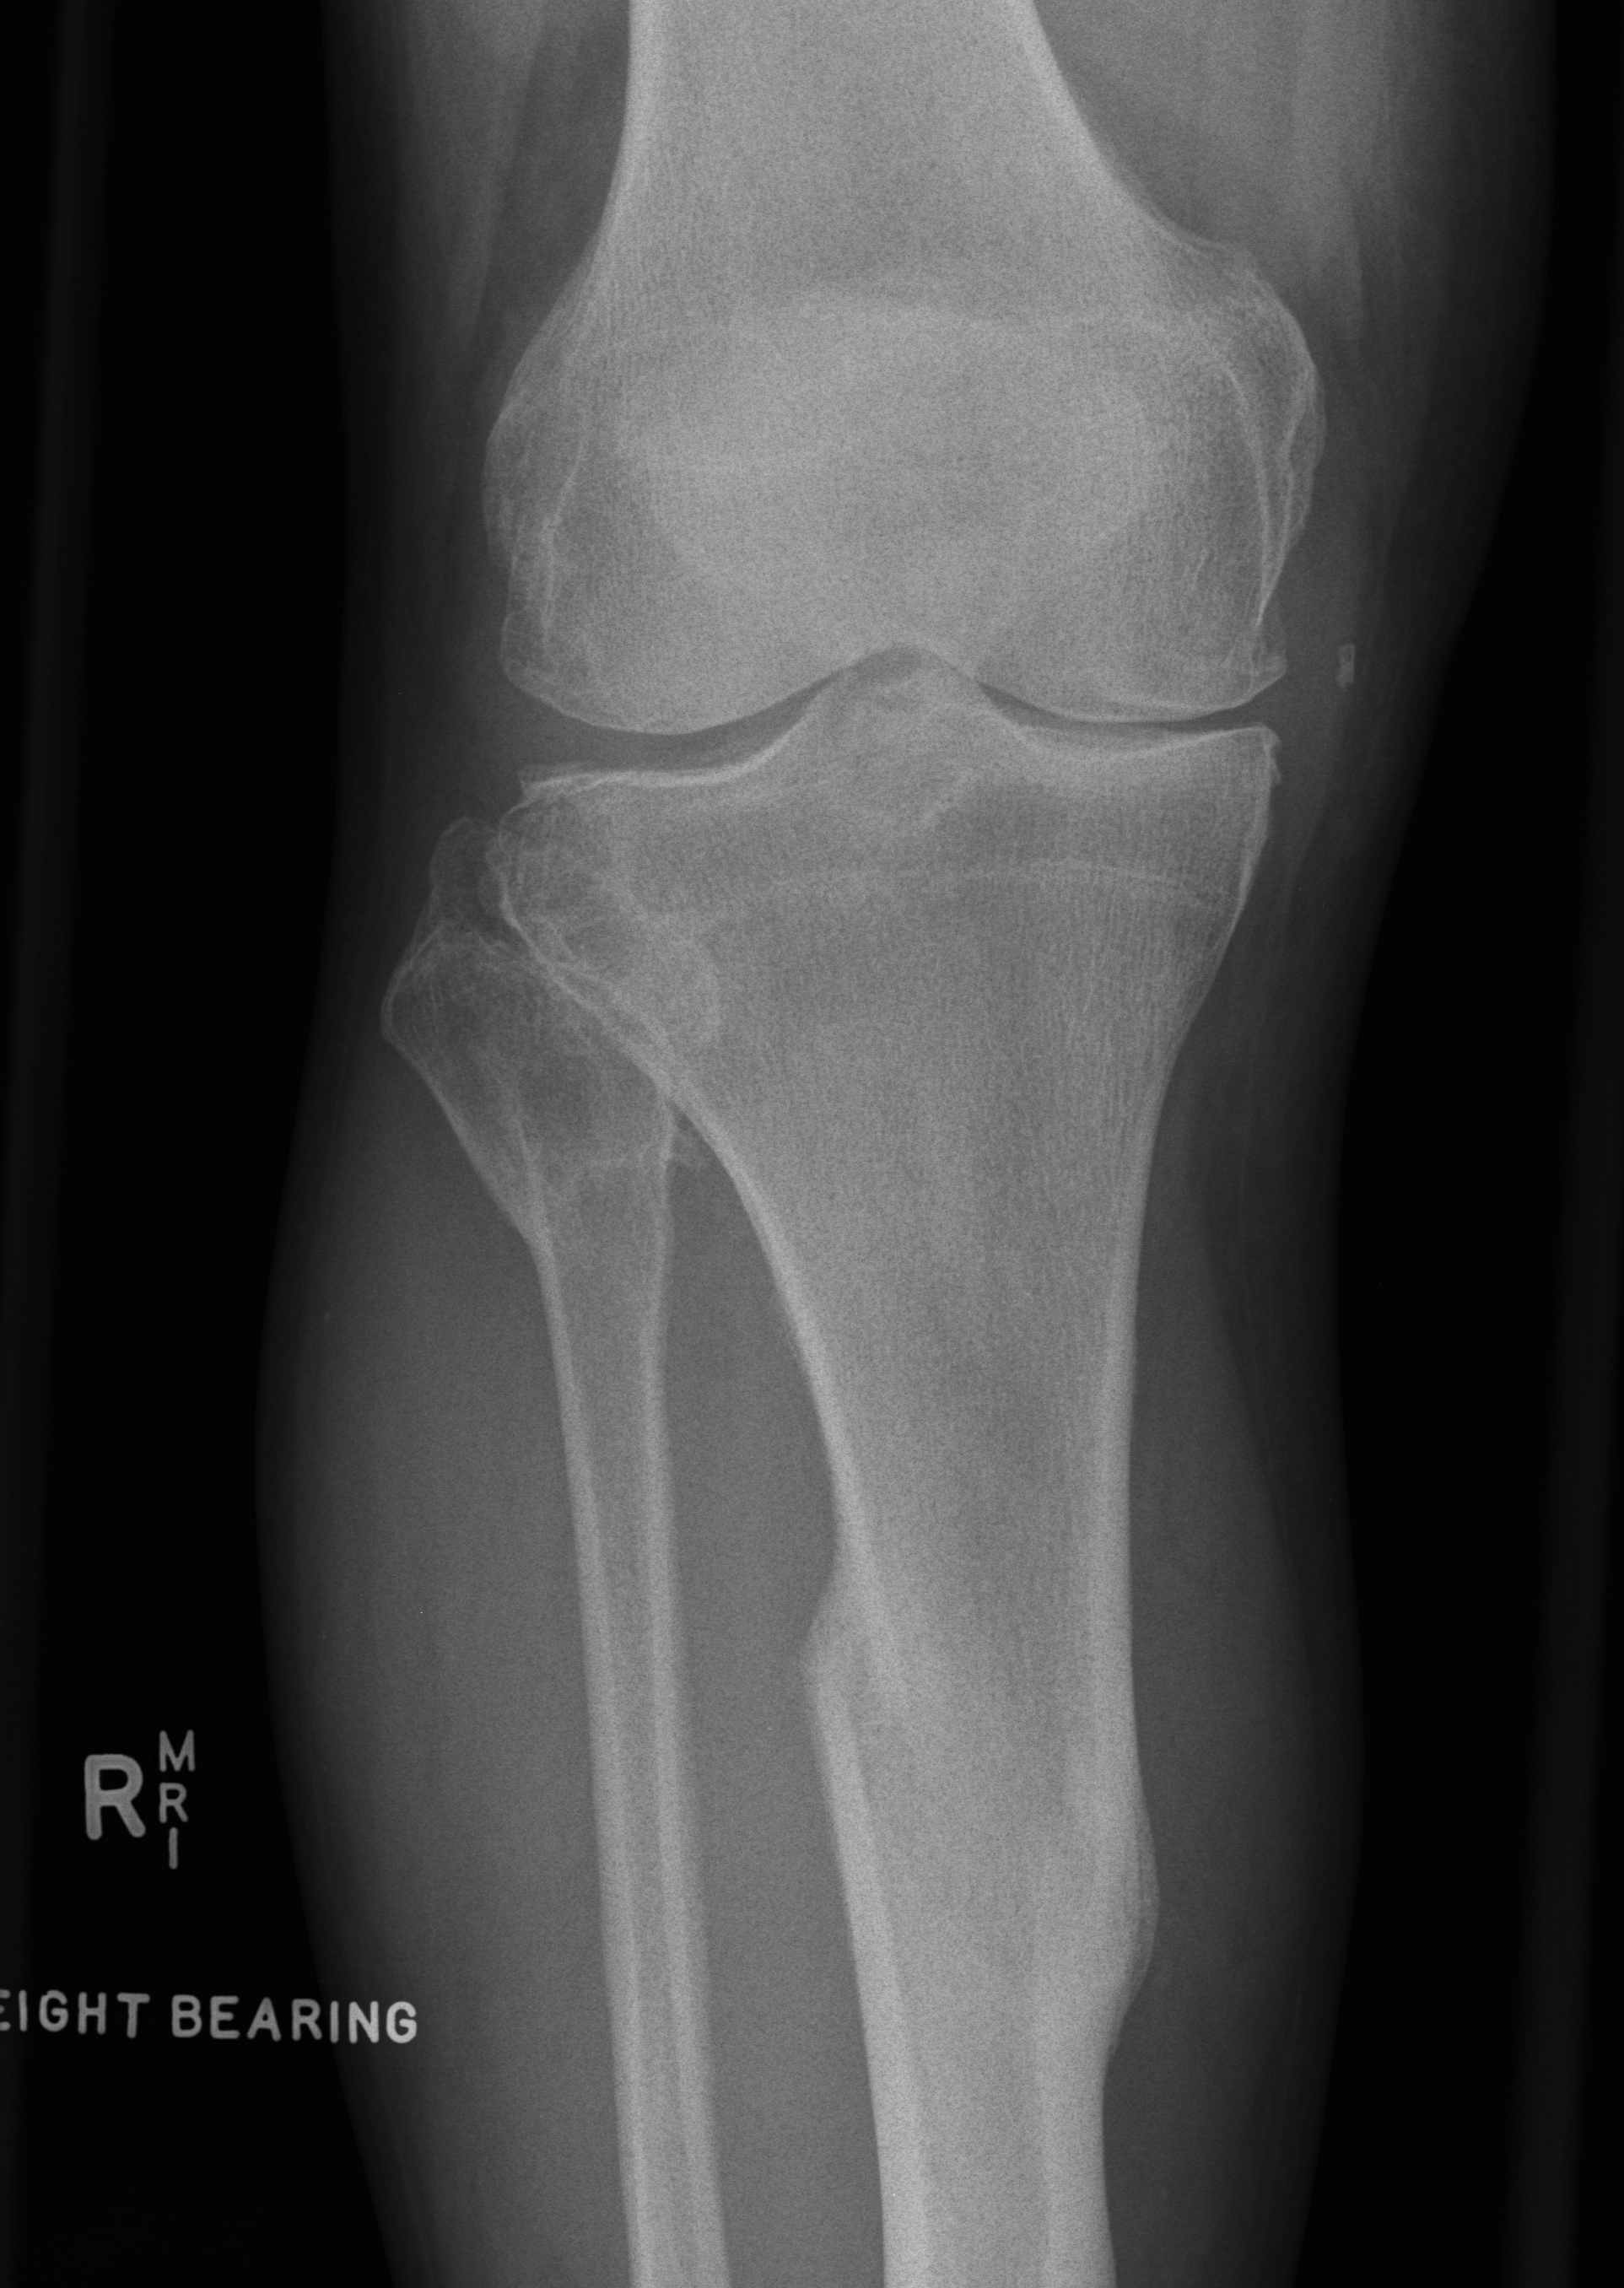

Indications

Unable to use femoral / tibial IM or EM Jigs

- fracture / metal work / deformity

Young patient < 65

- attempt to achieve perfect alignment / balancing

- want TKR to survive long term